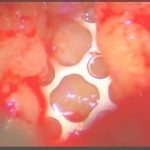

術中写真

摘出 後